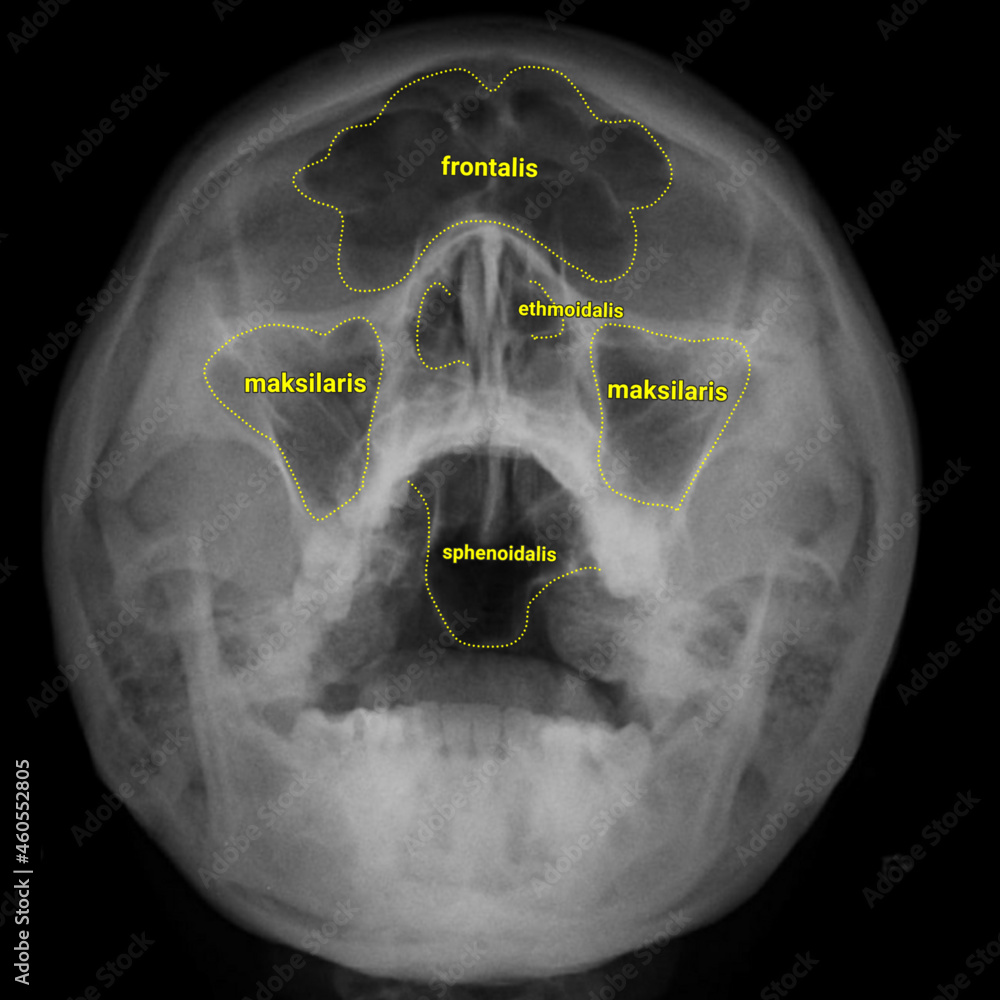

Waters View X Ray Anatomy . Lateral view, caldwell’s view, waters’ view, and submentovertex or base view. This page contains radiographic anatomy of the adult facial bones. The standard radiographic sinus series consists of four views: Occipitofrontal view (caldwell view) occipitomental (om) or waters view.

Lateral view, caldwell’s view, waters’ view, and submentovertex or base view. Occipitofrontal view (caldwell view) occipitomental (om) or waters view. This page contains radiographic anatomy of the adult facial bones. The standard radiographic sinus series consists of four views:

Waters xray paranasal sinus anatomy Stock Vector Adobe Stock Waters View X Ray Anatomy Occipitofrontal view (caldwell view) occipitomental (om) or waters view. Lateral view, caldwell’s view, waters’ view, and submentovertex or base view. The standard radiographic sinus series consists of four views: This page contains radiographic anatomy of the adult facial bones. Waters View X Ray Anatomy.